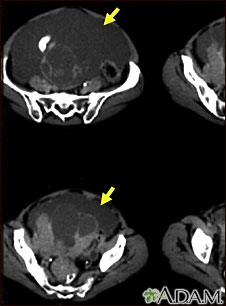

This CT scan of the lower abdomen shows a massive amount of free abdominal fluid (ascites) in a patient with ovarian cancer.